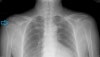

일반적인 X-ray에서는 정상 소견을 보입니다.

양측 손목에 5kg의 추를 매달고 찍는 부하 촬영(both shoulder stress view)에서 상완 골두가 하방으로 아탈구 또는 탈구되는 소견을 보입니다.

상완골두가 견갑와(glenoid)의 반 이상을 벗어나면 확실히 불안정성이 있다고 봐야합니다.

X-ray : 어깨 다방향성 불안정성(Multidirectional shoulder dislocation)